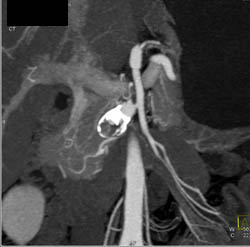

Partial Portal Vein Thrombosis (PVT) and Splenic and Superior Mesenteric Vein (SMV) Thrombosis